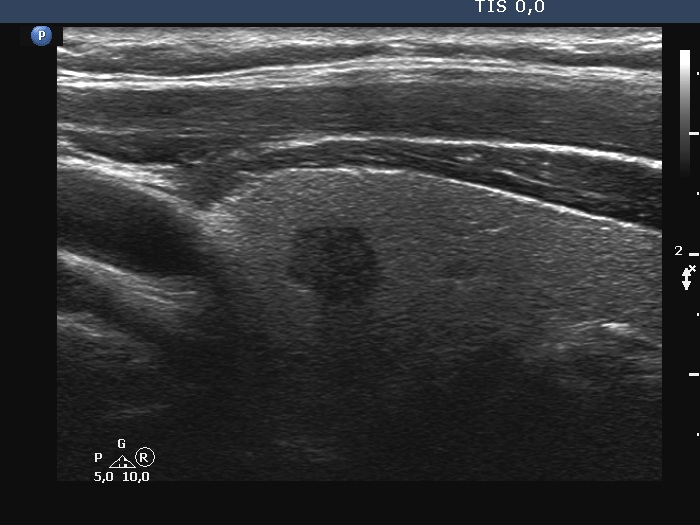

Ultrasonography. The thyroid was echonormal. There was a hypoechoic lesion in the right lobe. The lesion presented irregular borders and no vascularity. The size of the nodule was 7x6x8 mm, width, depth, length, respectively.

It is worth comparing the test performed at a higher and lower frequency. It's not just obesity, it can worsen image quality (the patient had an average build). In men, probably the different consistency of connective tissue and/or muscle tissue often impairs the penetration of ultrasound.

The absolute measure of surface irregularities was not high, however, it is worth comparing the degree of undulations to the size of the nodule. I regard this as pathological lobulation.